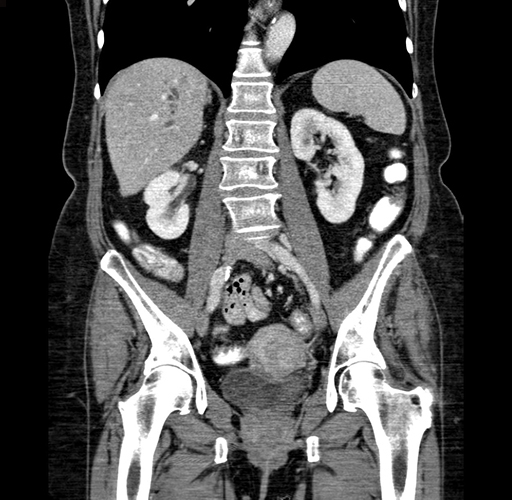

Axial Venous

Coronal Venous